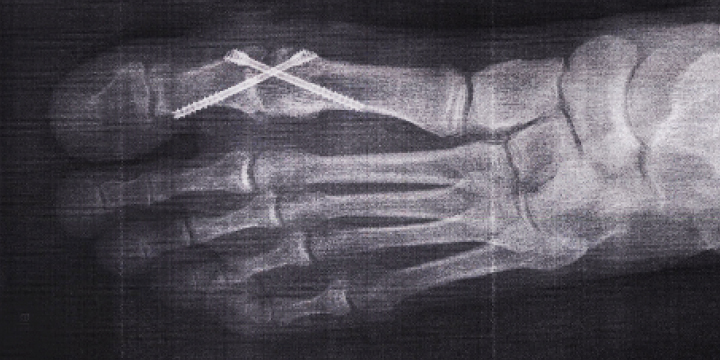

Nun, wie wird das gemacht? Auf die brutale Art! Es werden zwei Schrauben zueinander diagonal in den Zeh reingebohrt, das sieht aus wie ein X. Diese beiden Schrauben halten die Knochen fest zusammen und infolgedessen wird dann auch der Schmerz aufhören, weil keine Reibungsbewegung mehr stattfindet. So die Theorie und so hat es mir auch der Fußchirurg Dr. Mayer verklickert. Dazu muss der Zeh aber wieder seitlich aufgeschlitzt werden, wie damals vor zwei Jahren. Oh Gott, meine schöne rosa Narbe! Und die Kreuzspinnen werden wieder kommen!

Das ist in der letzten Woche gemacht worden. Als ich aus der Narkose aufgewacht bin, war der Fuß bis zum Schienbein dick verbunden und ich durfte mich nur noch mit Krücken fortbewegen. Einen Tag später musste ich zur Operationskontrolle in die Praxis, dort wurde der Zeh fotografiert. Weil ich in die Praxis ohne die Krücken gehatscht war, nur mit dem medizinischen Skistiefel, blaffte mich Dr. Mayer an. „Herr Zinkl, wo sind die Krücken? Sie spielen mit dem Operationsergebnis!“ Ich verspürte Angst und Schrecken, aber ein Blick auf das spektakuläre Schrauben-X-Röntgenfoto beruhigte den Doktor und erst recht mich. Alles im grünen Bereich. An dieser Stelle bedanke ich mich hundertausend Mal bei meiner allerliebsten Alexandra, die mich mehrmals transportiert und bekocht und betüdelt hat. Sie ist ein wahres Glück für mich, in jeder Hinsicht.